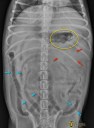

Et celui-là, qu’a-t-il ingurgité ?

18 mai 2014